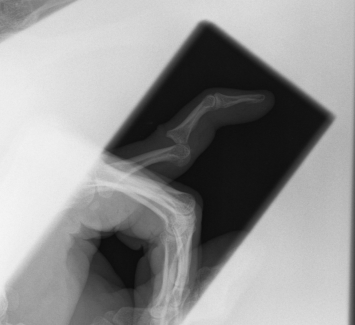

This weekend I had a… little mishap on the bike.